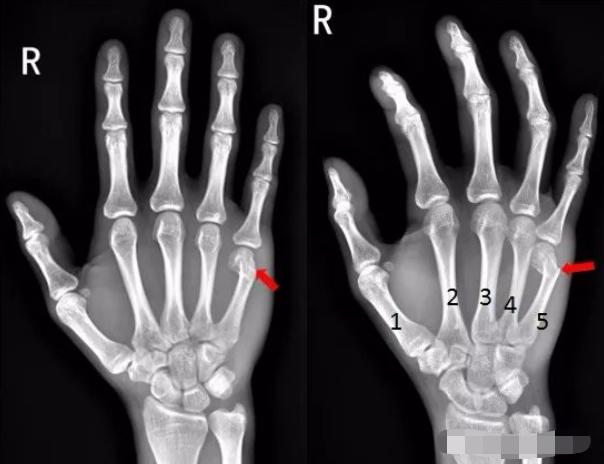

4、患者中指提重物受伤,拍片如下:

右手中指远节近端背侧关节处见游离骨片影,右手中指远节骨折。

5、患者酒后右手砸墙,拍片如下:

右手第五掌骨远端骨皮质不连续,骨折端移位、成角。右手第五掌骨骨折(1-5. 第1-5掌骨)